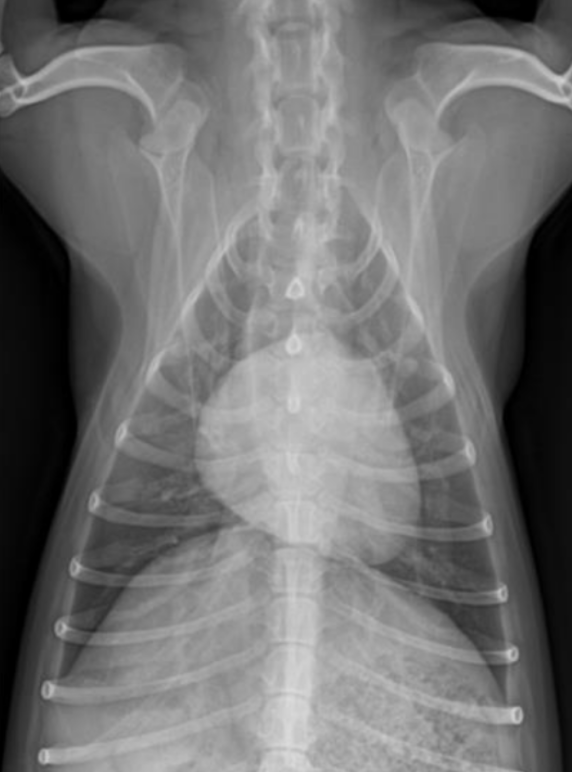

| DV (Dorso-ventral) | VD (Ventro-dorsal) |

![]() | ![]() |

| ์ฌ์ฅ ๊ด์ฐฐ์ ์ข์. | ํ ๊ด์ฐฐ์ ์ข์. |

| ๊ธฐํ ์์ ๋ ์ข์. (pleural air) | ํ์ ์์ ๋ ์ข์. (pleural fluid) (๋ฐ๋ฅด๊ฒ ๋์ธ ์ผ๊ฐํ ๋ชจ์ - ํ์๊ฐ ์๋-์์ผ๋ก ํผ์ง) |